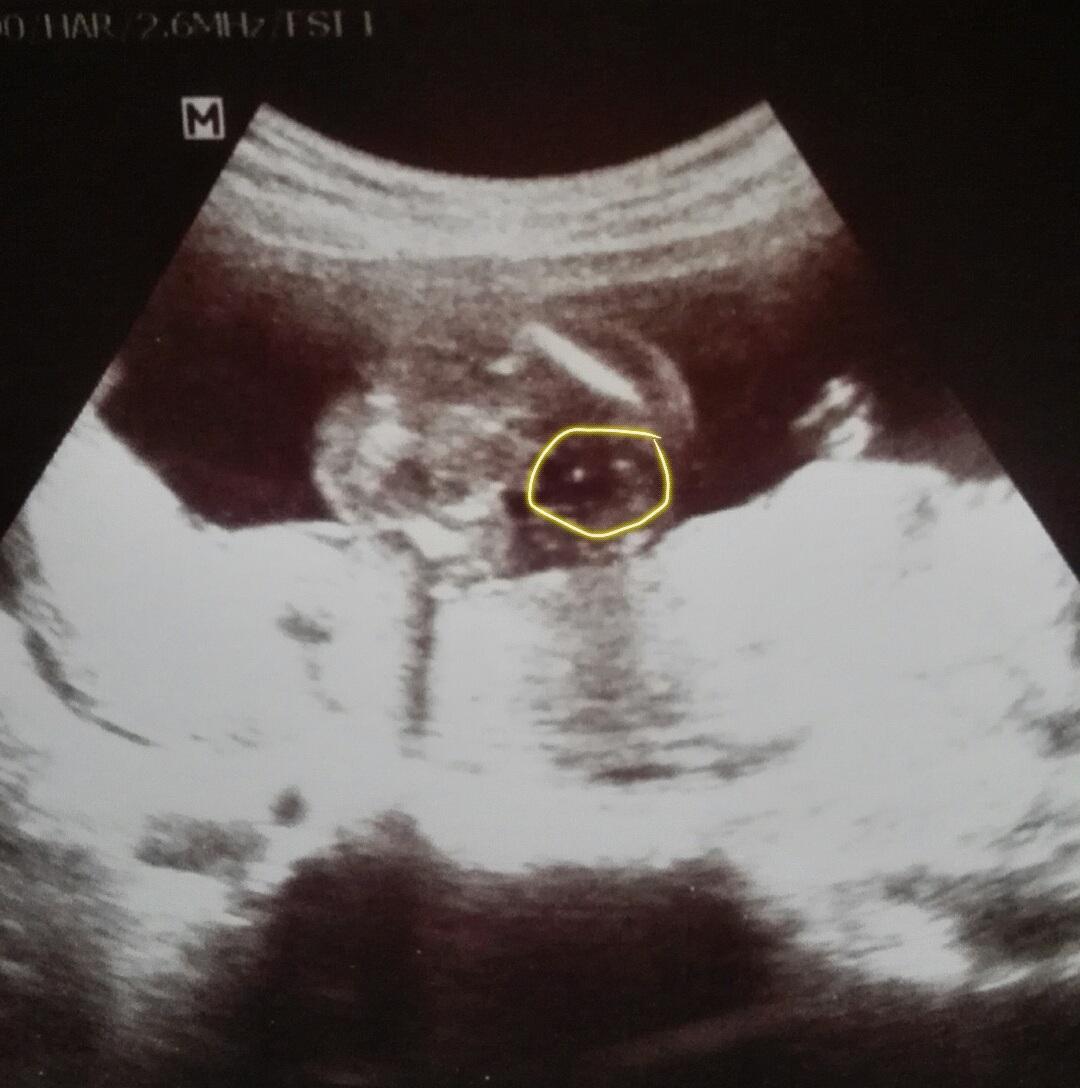

@juliemichal A ty už máš chlapečka potvrzeného? Tak to budeme pravděpodobně na stejné vlně, 3 kluci :-*. Na té tvé fotce to je označen pytlík i pindík?

@rennye ano ano už ho mám na 100% potvrzeného s dnešního screeningu 😀 na té mé fotce je jen označen pytlík 😀 pindíka měl schovaný za pupeční šňůrou 😀

@jarpa111 pindu nevidim,ale kulicky to byt muzou,ma nohy u sebe 😉 to,co jsi zakrpuzkovala je zadecek.